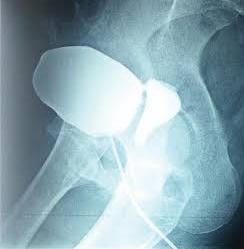

A cystogram or a voiding cystourethrogram(filing d bladder with contrast & taking an Xray while d pt urinates)is necessary fr diagnosis. CT urogram is necessary 2 diagnose ureterovaginal fistula. In addition,a cystoscopy (looking at d inside of d bladder through a scope) is done.

Here in d image posted in d morning, U can see d Urinary Bladder anteriorly, the fistulous track at the top, and the Vagina at the posterior aspect. So contrast given into the bladder, which shd remain in the bladder is seen passing through the abnormal fistula into the Vagina.